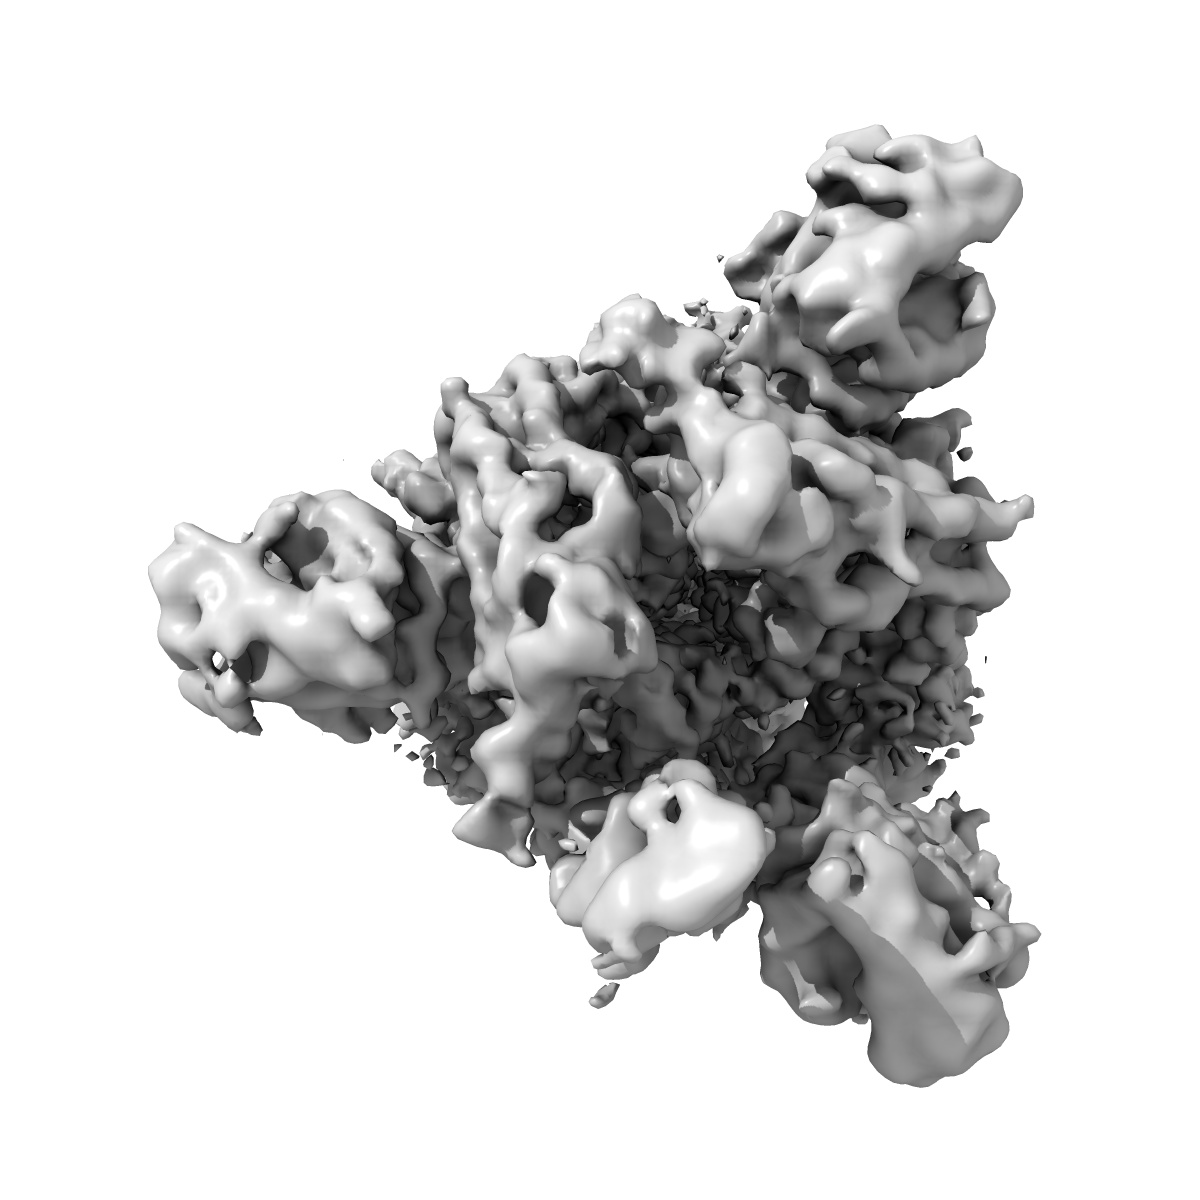

Cryo-EM structure of SARS-CoV-2 Spike Proteins on intact virions: Alpha (B.1.1.7) variant 1 open RBD

Virion morphology and on-virus spike protein structures of diverse SARS-CoV-2 variants.

Ke Z , Peacock TP , Brown JC , Sheppard CM , Croll TI , Kotecha A , Goldhill DH , Barclay WS , Briggs JAG

(2024) EMBO J , 43 , 6469 - 6495